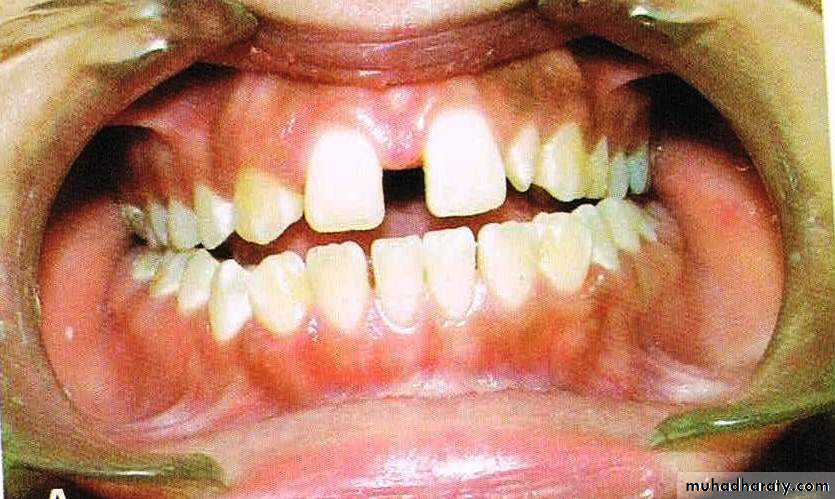

MIDLINE DIASTEMA

DEFINATION OF DIASTEMAA space between adjacent teeth is called a diastema.

DEFINATION OF MIDLINE DIASTEMAMidline diastema refers to anterior midline spacing between the two central incisors.

b) Mesiodens

Presence of an unerupted mesiodens between the two central incisors also predispose to midline diastema.56

c) Abnormal labial frenum

The presence of a thick and fleshy labial frenum can cause a midline diastema.This type of fibrous attachment can prevent the two maxillary central incisors from approximating each other.